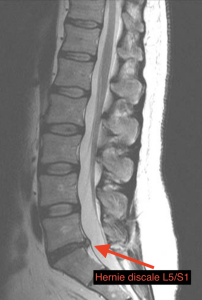

Comme cette douleur est chronique et devient invalidante, nous avons prescrit une IRM LOMBAIRE (MRI) pour éliminer tout facteur grave et permettre d’avoir un traitement des plus précis.

L’IRM montre une hernie discale postero-lateral L5/S1 droite avec compression de la racine nerveuse S1. (Dans ce cas-là, nous avons affaire à une sciatique liée à une compression nerveuse à cause d’un disque, il existe de nombreuses autres origines aux sciatiques.)